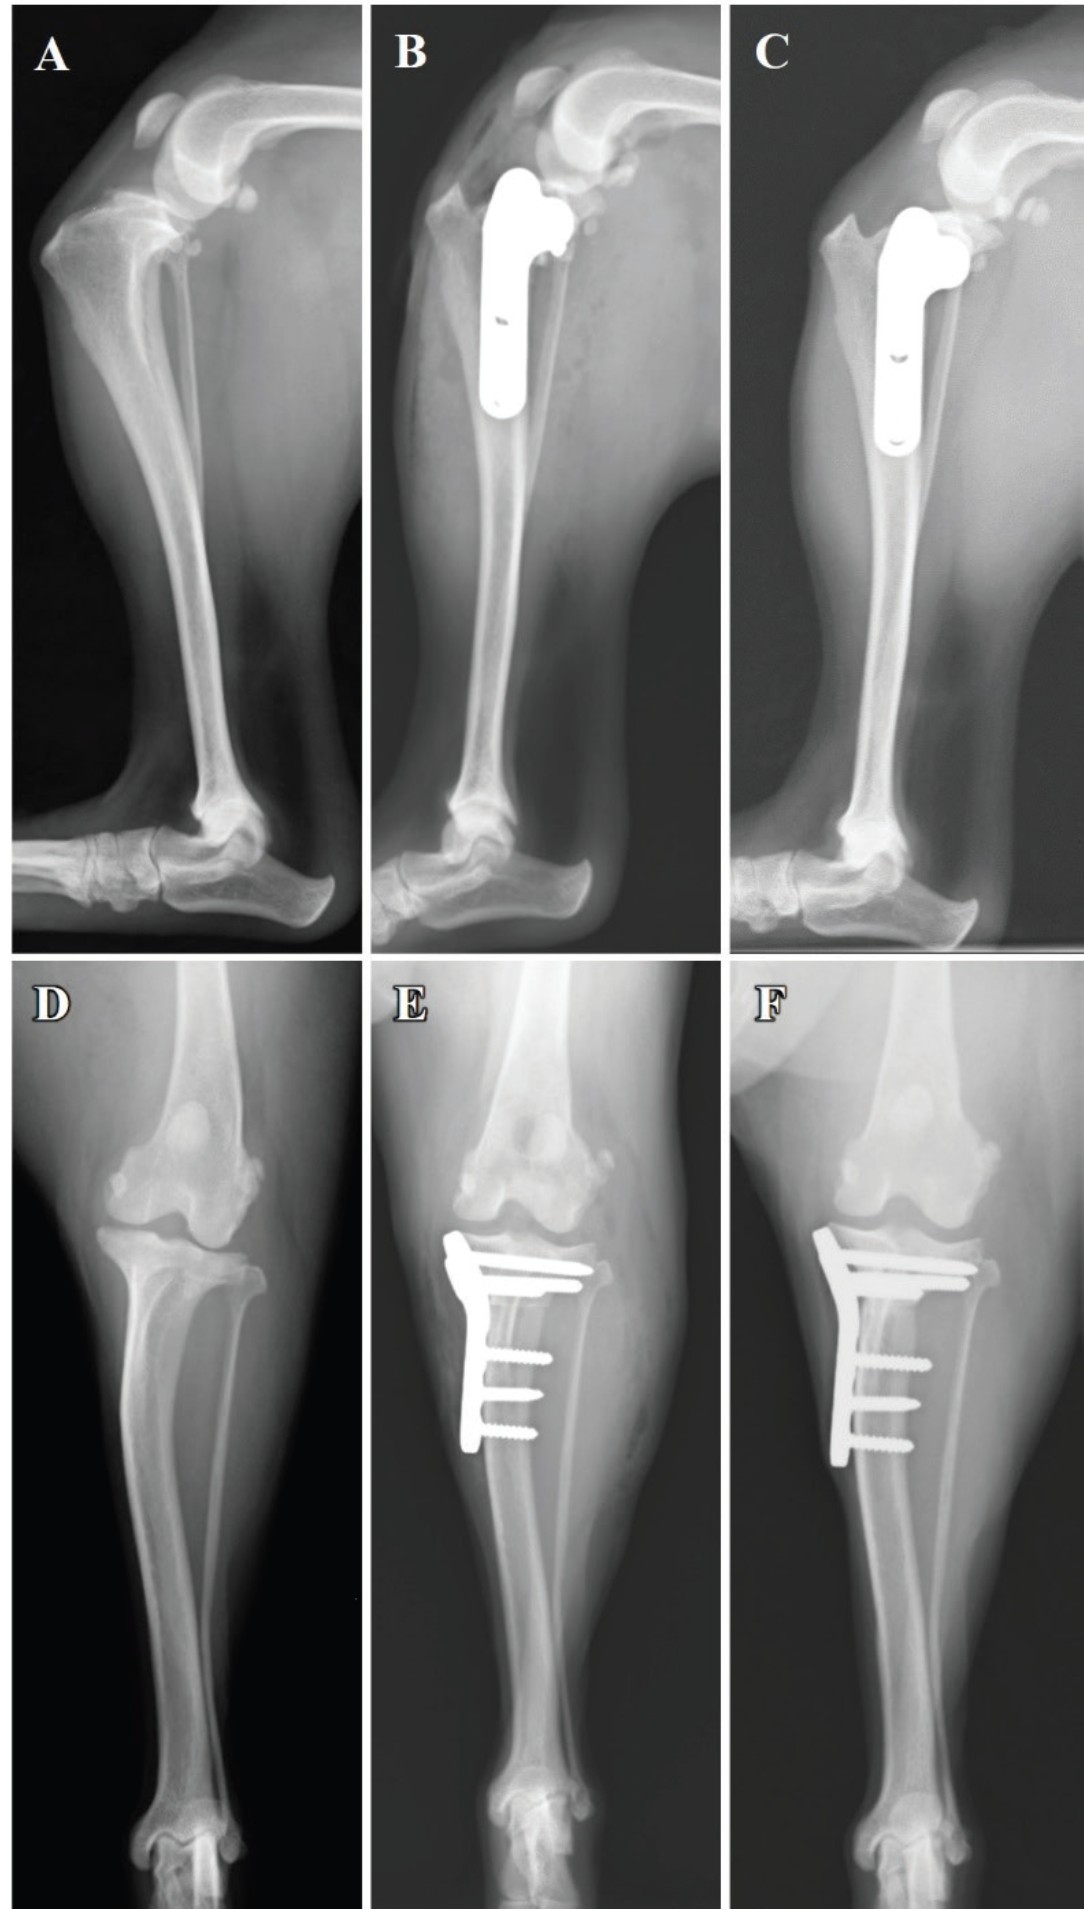

右膝关节X光显示髌下脂肪垫征象和胫骨向前移位(图1A)。未观察到明显的肢体畸形(图1A和D)。

图1. 右肢的侧位X光片(A-C)和后前位X光片(D-F)。首次就诊时的髌下脂肪垫征象和胫骨向前移位(A),未见肢体畸形(D)。放置2.4毫米TPLO钢板(B和E)。术后14周随访时未见截骨线(C)。术后14周TPLO随访时未见脱位(F)。

术后X光检查后,全麻下应用改良的罗伯特·琼斯绷带(图1B和E),并维持2天。术后24小时口服非甾体抗炎药非罗考昔5 mg/kg,以及头孢唑啉20 mg/kg,每12小时一次,持续5天。

术后14周,右后肢(左后肢术后4周)在醒来时有轻微不适;行走或小跑时未观察到跛行。两侧的胫骨压缩试验结果均为阴性,右后肢的旋转骨片与胫骨完全融合(图1C和F)。左后肢的胫骨可见微弱的截骨线。X光显示右侧和左侧的骨或TPLO植入物均无脱位。主人对行走能力的显著改善感到满意。